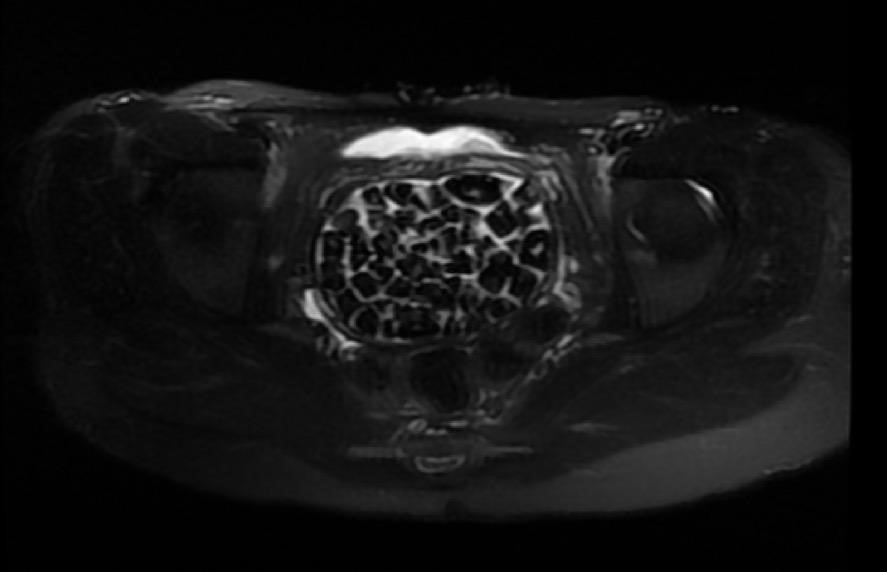

Hastasının durumuna yönelik konuşan Üroloji Uzmanı Doç. Dr. Erkan Erkan, "Hastamızın 2004 yılında doğduğunu ardından doğar doğmaz ekstrofi vezika dediğimiz 50 binde bir görülen bir anomaliden dolayı art arda ameliyatlar geçirdiğini öğrendik. 10 yaşında yine bir ameliyat geçirmişti, gerekli görüntüleme ve tetkiklerimizi yaptırdık. Normalde mesanesinin olması gereken yerin hemen arka kısmında taşlarla dolu bir kese olduğunu gördük, bunun üzerine ek görüntülemeler; MR çektirdik. Hastamız çelişkili açıklamalar almıştı, kendi radyolojik kliniğimiz ve edindiğimiz konsültasyonlarda taşların mesanede değil vajinal boşlukta oluştuğunu düşündük, bir planlama yaptık. Kadın doğum hocamızın da çabasıyla taşları tamamen temizledik ardından ileride normal bir hayat sürmesi bakımından oraya plastik cerrahi yaptık. 287 adet taş çıkardık, pratikte gerçekten görünce çok şaşırdık çünkü bu aynı zamanda literatürde çok nadir görülen bir olay. Biz ameliyata hazırlanırken de teorik olarak biraz araştırdık. Literatürde gördüğümüz kadarıyla buna benzer bu tanıma uyan bir vaka vardı. Literatürde sanırım yayınlanmış 2’nci vaka olacak. Farkındalık çok önemli, bilinçli bir hastamız vardı. Doğumsal anomaliyle doğan çocuklarımızda ileride bunlara bağlı bazı sıkıntılar çıkabileceğinin öngörülmesi lazım. İlgili tedavilerini alsalar bile düzenli takiplere gelmeleri gerekiyor. İleride eğer dikkat etmezse ki zannetmiyorum, tekrarlayabilir. Bu rahatsızlık ekstrofi vezikal epispadias durumu çok nadir bir durum" dedi.

Genç kızın uzun süredir devam eden karın ağrısı olduğunu söyleyerek sözlerine başlayan Jinekolojik Onkoloji Uzmanı Op. Dr. Emin Erhan Dönmez, "Mesane taşları olduğu düşünülerek daha büyük bir hastaneye refere edilmiş. Aramızda mini bir konsey yaparak muayene ettik. Vajen bir hazne görevi görerek orada durağan bir idrar, uzun süre beklediği için idrar içindeki minerallerde çökerek taşlar oluşmuş. Mesanedeki idrarın vajene akmış olabileceği ve vajende göllenen idrar nedeniyle taşların burada oluşacağını düşündük, ameliyatımızı planladık. Ameliyata tanı amaçlı girmiştik, sistoskopi (Mesane gibi idrar yollarını kapsayan kısımlardaki rahatsızlıkların teşhis ve tedavisinde kullanılan endoskopik bir yöntem) dediğimiz ameliyatı Erkan Hocam ile birlikte gerçekleştirdik. Önce mesaneyi bir görüntüledik, mesane tabanına yaklaşık 2-3 cm’lik bir alandan vajene fistülize olduğunu gördük. Mesaneden vajene geçtiğimiz esnada tüm vajenin taşlarla dolu olduğunu gördük. Tanı amacıyla girdiğimiz ameliyatta her şey de olağan gittiği için tedaviye geçtik. Taşların çıkabileceği kadar bir genişlik sağladık. Daha sonra yaklaşık en büyüğü 2,5 cm boyutlarında olan, irili ufaklı 287 tane taşı ameliyat esnasında çıkarmış olduk. Taşların tekrarlamaması için idrarın göllenmemesi, en azından dışarıya rahatça boşalabilmesi için vajinal rekonstrüksiyonu sağladık. Ameliyatta da herhangi bir problem yaşamadık. Literatürü Erkan Hocam ile birlikte değerlendirmiştik. Primer olarak vajende birikmiş olan bu kadar çok sayıda taşla ilgili bir makale görmedik, rastlamadık" dedi.